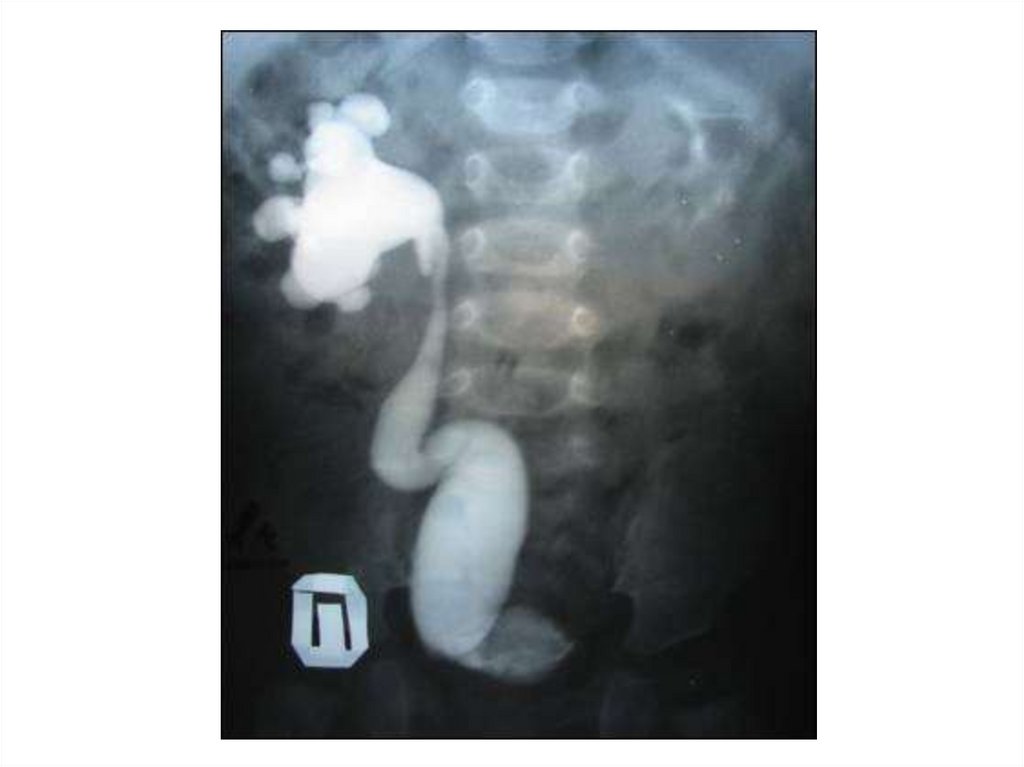

Гидронефротическая трансформация

Пиелэктазия

Уретерогидронефроз